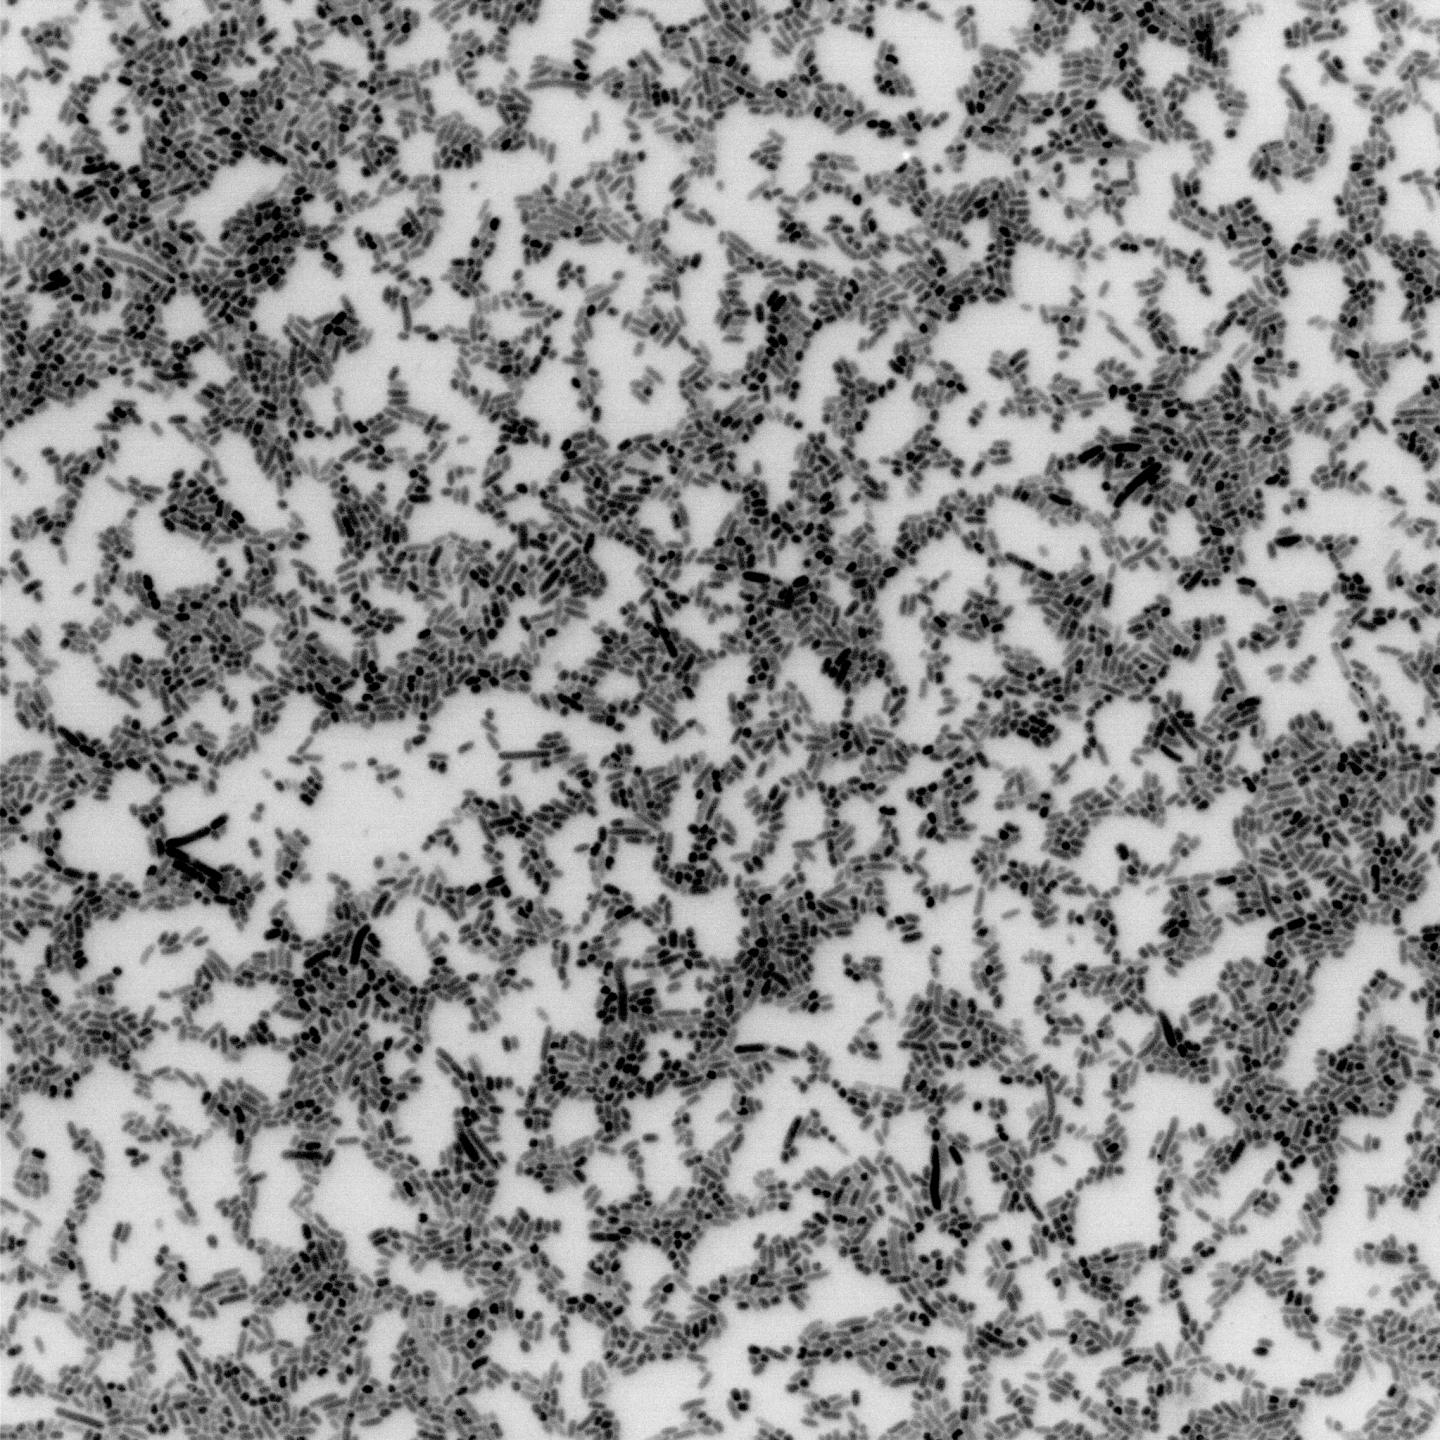

这些微生物(图中包含了五种细菌)被称为肠道微生物组,在人们的健康中发挥着关键作用

人体肠道中充满了细菌。每克粪便含有约1000亿个细菌细胞,肠道细菌的数量与人类细胞的数量比例高达10:1。这些微生物(统称为肠道微生物组)承担着各种各样的工作,Mougous说。他们消化食物,保持肠道表面完整,提供维生素,并排除有害细菌。“肠道微生物组对人类健康非常重要——我们当然要了解清楚。”